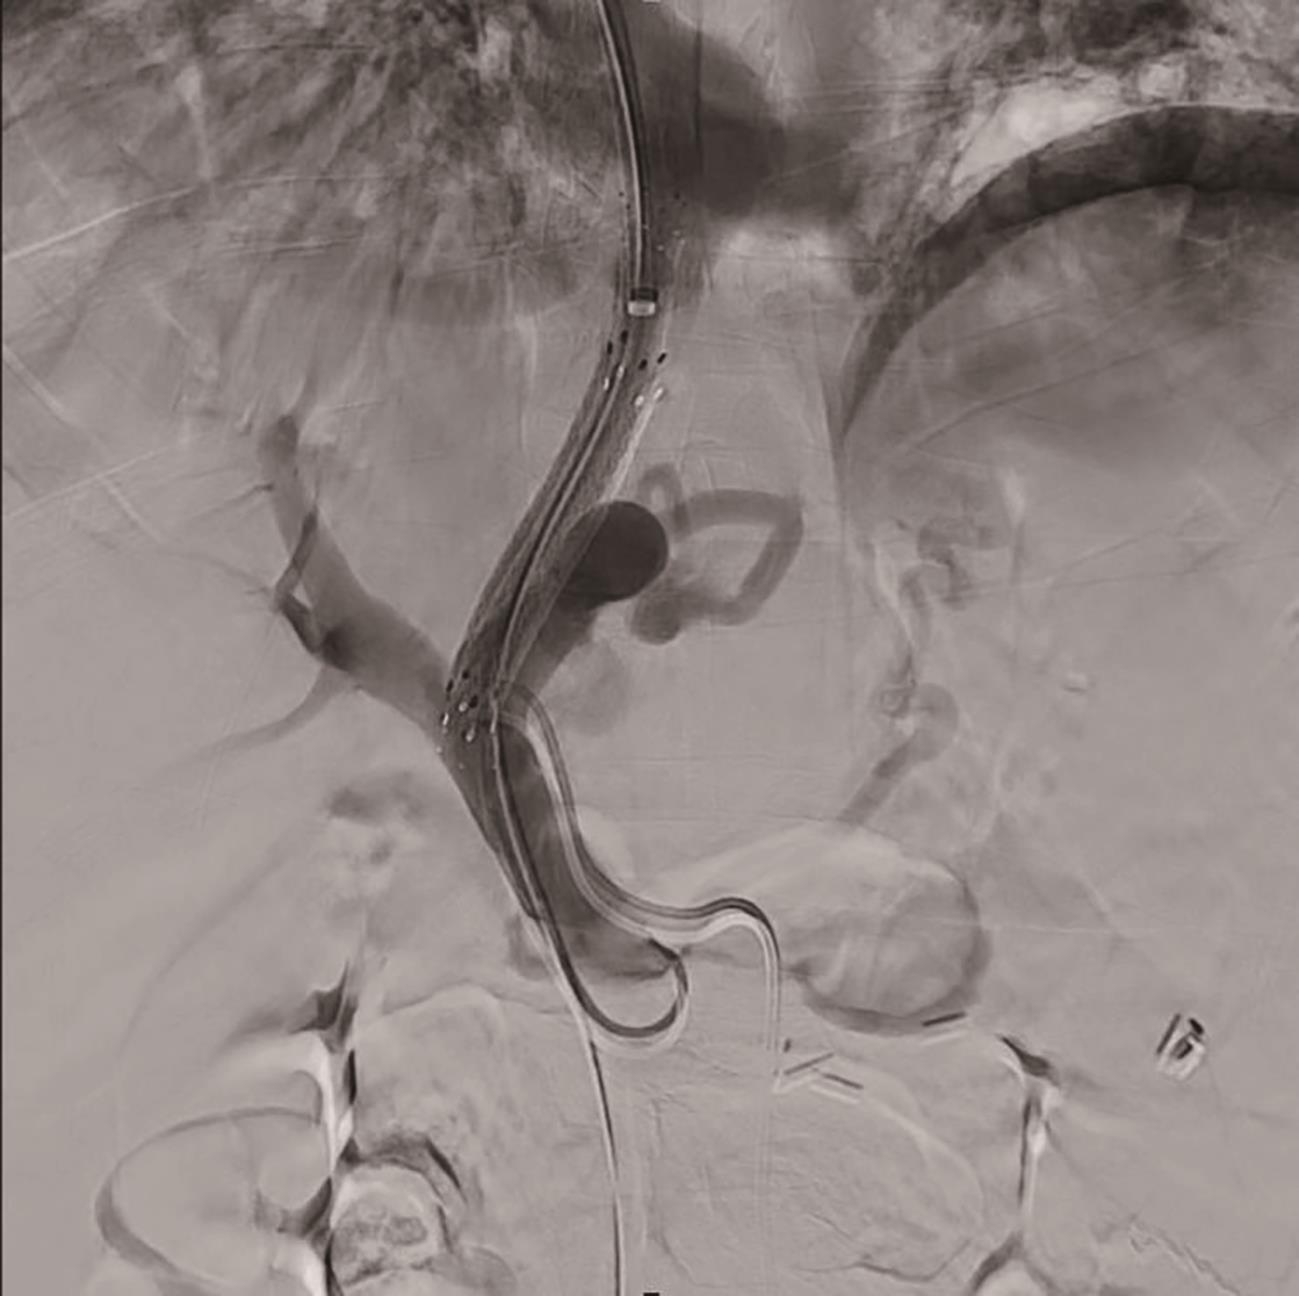

Risk factors for unplanned readmission after transjugular intrahepatic portosystemic shunt in cirrhotic patients with esophagogastric variceal bleeding and construction of a nomogram model

Qin YIN, Zhaorong WU, Feng ZHANG, Chunyan JIN, Yanping CAO, Jiangqiang XIAO, Yuzheng ZHUGE, Qian WANG

2024, 40(9): 1796-1801. DOI: 10.12449/JCH240913

Abstract(1137) HTML (1363) PDF (1108KB)(72)

Abstract:

Objective  To investigate the risk factors for unplanned readmission within 30 days after discharge in cirrhotic patients with esophagogastric variceal bleeding undergoing transjugular intrahepatic portosystemic shunt (TIPS), and to construct a nomogram predictive model.  Methods  A total of 241 cirrhotic patients who underwent TIPS due to esophagogastric variceal bleeding in Affiliated Drum Tower Hospital of Nanjing University Medical School from January 2020 to June 2023 were enrolled as subjects, and unplanned readmission within 30 days was analyzed. According to the presence or absence of unplanned readmission, they were divided into readmission group with 36 patients and non-readmission group with 198 patients, and related clinical data were collected from all patients. The independent-samples t test was used for comparison of normally distributed continuous data between two groups, and the Mann-Whitney U test was used for comparison of non-normally distributed continuous data between two groups; the chi-square test was used for comparison of categorical data between two groups. A logistic regression analysis was used to identify independent risk factors for unplanned readmission. A nomogram prediction model was constructed, and the receiver operating characteristic (ROC) curve was plotted to assess its discriminatory ability for unplanned readmission; the calibration curve was plotted to evaluate the consistency of the nomogram model in predicting unplanned readmission; the ResourceSelection package of R language was used for the Hosmer-Lemeshow goodness-of-fit test to evaluate the degree of fitting of the mode; the decision curve analysis was used to investigate the practicality of the model.  Results  Age (odds ratio [OR]=2.664, 95% confidence interval [CI]: 1.139‍ ‍—‍ ‍6.233, P<0.05), CTP score (OR=1.655, 95%CI: 1.098‍ ‍—‍ ‍2.495, P<0.05), and blood ammonia (OR=1.032, 95%CI: 1.016‍ ‍—‍ ‍1.048, P<0.05) were independent risk factors for unplanned readmission within 30 days after discharge in the patients undergoing TIPS. The multivariate analysis showed that for the nomogram predictive model constructed in this study, repeated sampling for 1 000 times using the Bootstrap method was performed for internal validation, and the area under the ROC curve was 0.773, which was significantly higher than that of age (0.582), CTP score (0.675), and blood ammonia (0.641). The calibration curve showed good consistency between the probability of unplanned readmission predicted by the nomogram model and the actual probability, and the Hosmer-Lemeshow goodness-of-fit test showed good degree of fitting (c2 =5.647 3, P=0.686 7).  Conclusion  Age, CTP score, and blood ammonia are independent risk factors for unplanned readmission within 30 days after TIPS, and the nomogram prediction model constructed based on these factors can help to predict the risk of unplanned readmission in TIPS patients and provide an accurate decision-making basis for early prevention.